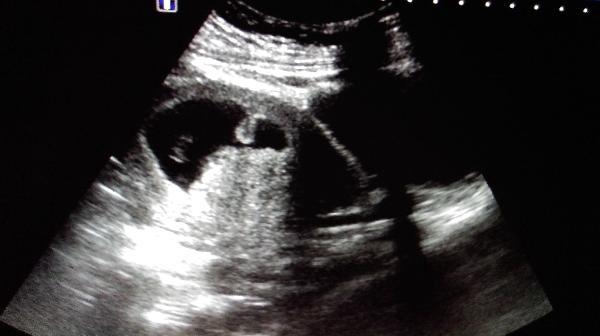

早孕9周妊娠囊这个形态怎么报?

妊娠囊近似葫芦状,胎芽、胎心、卵黄囊正常。孕妇原有子宫腺肌症,有痛经病史。

只要胎心正常,见卵黄囊,我们也认为是正常,妊娠囊的形态和膀胱充盈程度也有关系